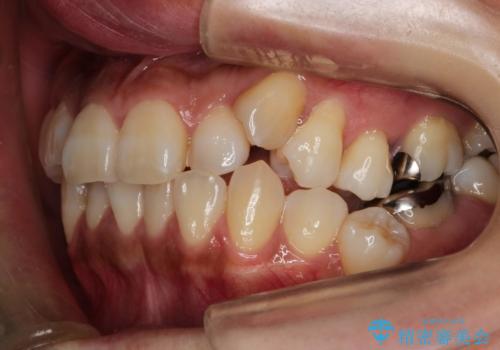

ハーフリンガル抜歯矯正 八重歯を改善する

- 小臼歯4本抜歯によるハーフリンガル・ワイヤー矯正を計画した。

シビアな八重歯がきれいに歯列にはいることにより、笑った時の印象などもかなり大きく変わります。